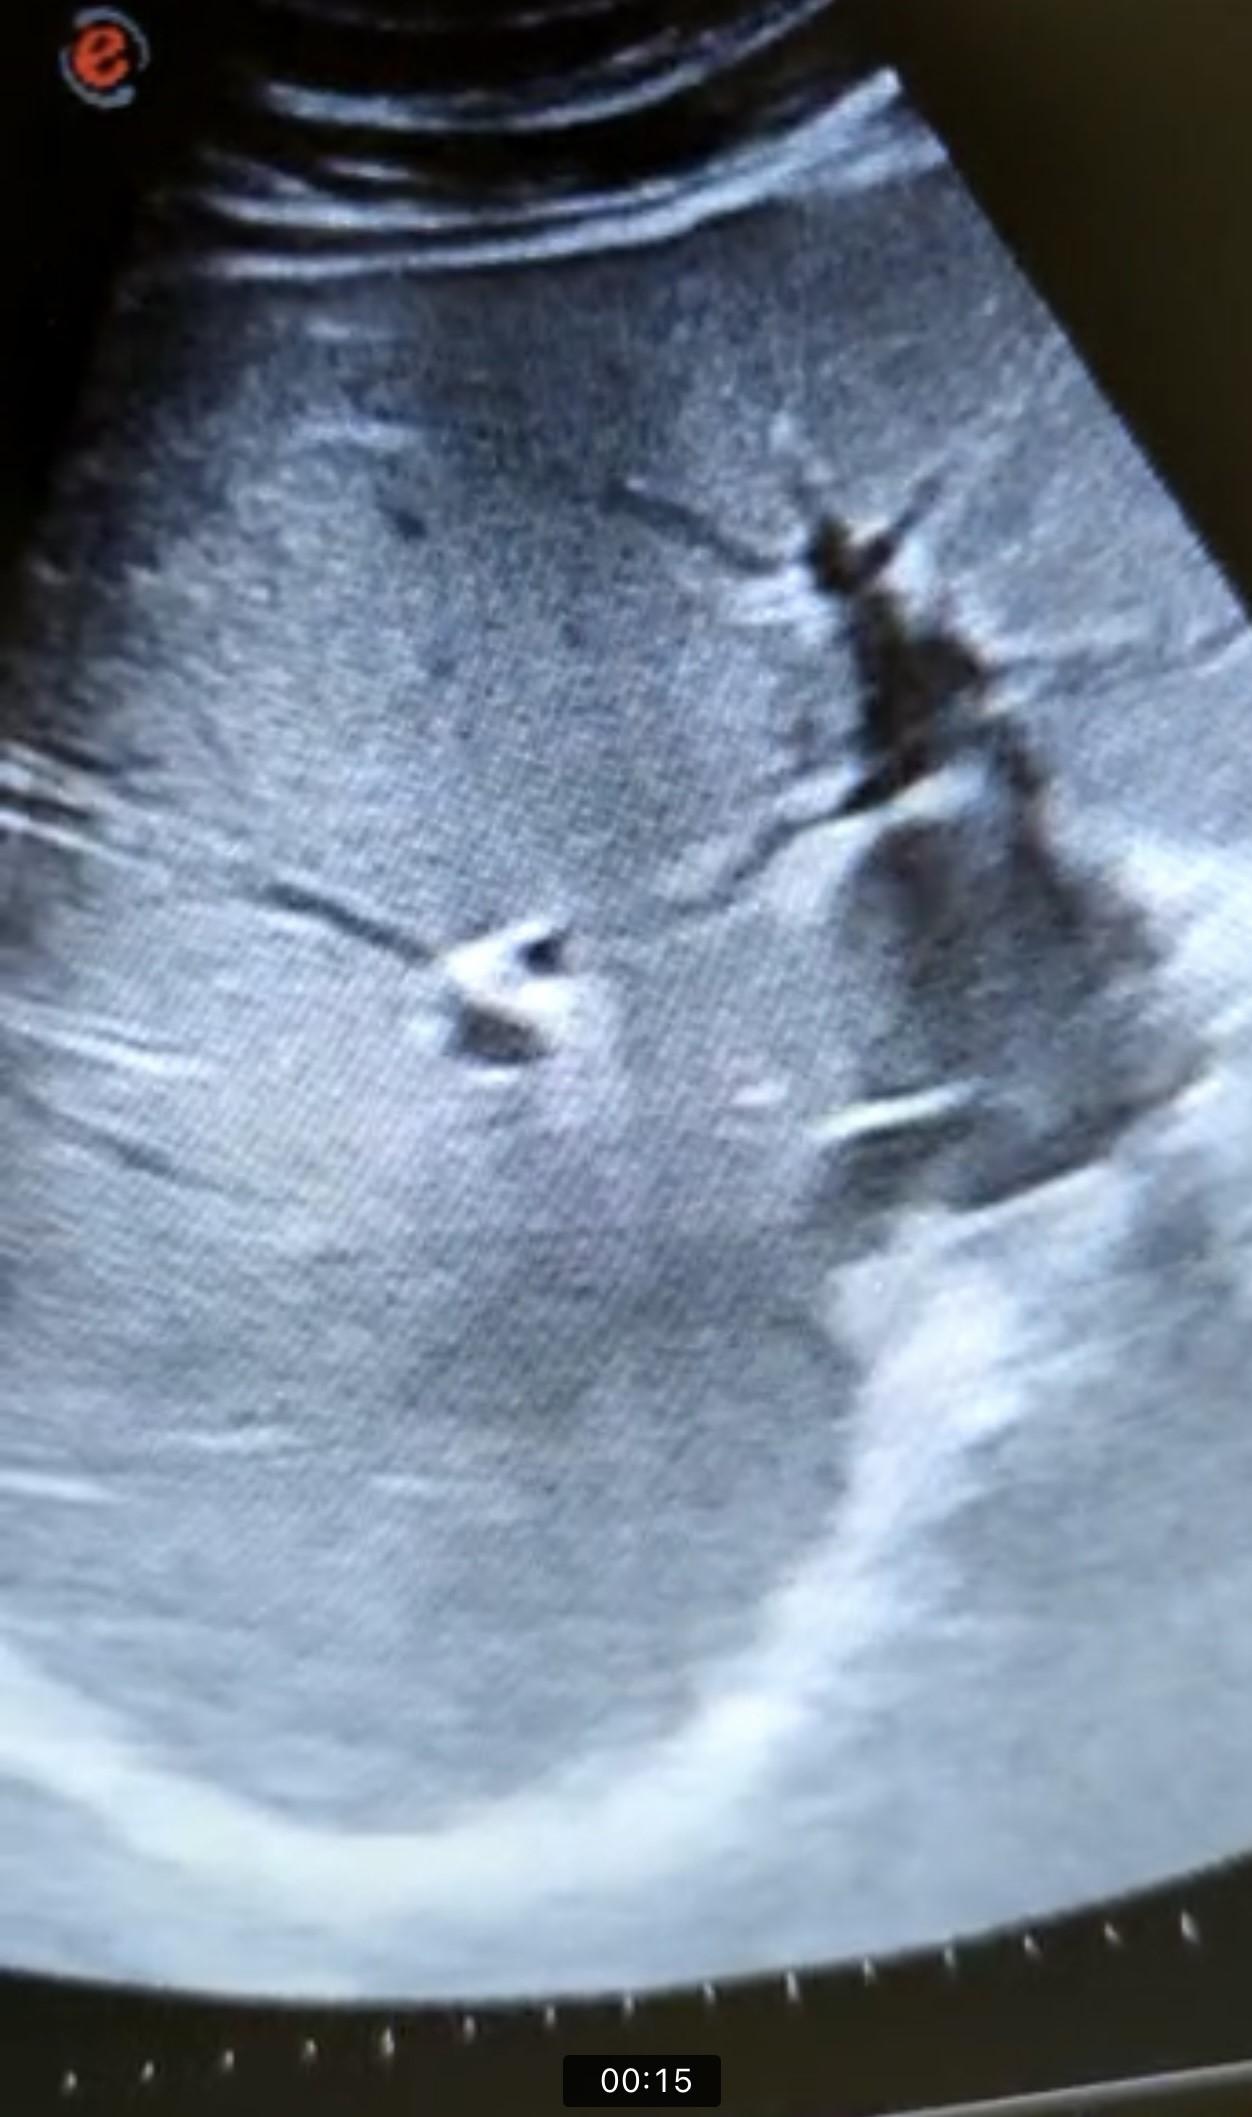

En la ecografía se observa ectasia de la vía biliar intrahepática conformando un patrón de doble carril.

No se visualizan colelitiasis.